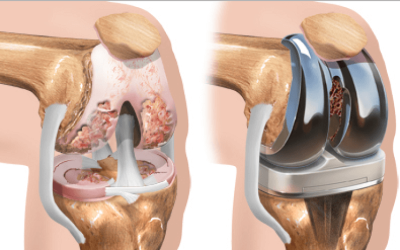

Phẫu thuật

Phẫu thuật được coi là biện pháp điều trị cuối cùng khi mà các cách khác không hiệu quả. Chi phí cao, quá trình hồi phục hoàn toàn sau phẫu thuật có thể kéo dài 4-9 tháng nhưng khoảng 3-4 tháng là hầu hết bệnh nhân có thể tiếp tục các hoạt động bình thường được rồi. Các can thiệp phẫu thuật bao gồm:

- Cắt khớp: Loại bỏ các khớp bị tổn thương, hợp nhất xương bằng các khớp nối như ghim, vít. Sau khi lành lại, cơn đau giảm rõ rệt và các xương vẫn liên kết được với nhau.

- Phẫu thuật nội soi: Loại bỏ sụn lỏng lẻo, các gai xương làm cản trở hoạt động của khớp. Thường không áp dụng trong tình trạng bị viêm, nhưng nó có thể hữu ích cho một số người.

- Thay thế toàn bộ mắt cá chân: Loại bỏ xương và sụn, sau đó thay thế bằng các bộ phận nhân tạo (mắt cá chân giả)

Tuy nhiên, trước khi tiến hành phẫu thuật bác sĩ luôn đưa ra những cảnh báo như thời gian hồi phục chậm và có tỉ lệ biến chứng cao. Vì vậy, phẫu thuật được thực hiện phải có sự đồng ý của bệnh nhân. Chính điều này khiến nhiều người lo ngại và chấp nhận điều trị bằng thuốc hoặc vật lý trị liệu trong thời gian dài.